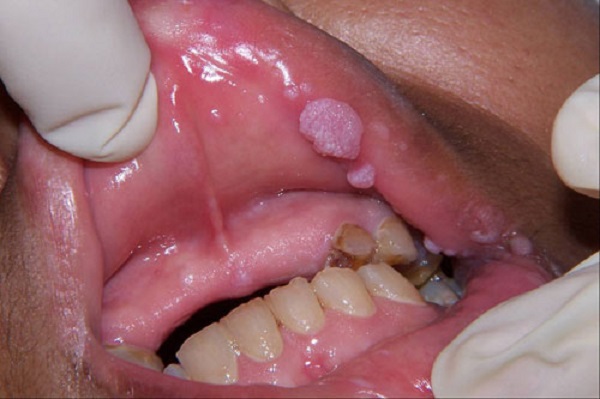

Hình ảnh sùi mào gà ở miệng

Chạm vào để xem ảnh

– Cũng giống với bệnh sùi mào gà nam giới, sùi mào gà ở nữ giới còn xuất hiện ở miệng, mắt, họng, lưỡi,..

Hình ảnh sùi mào gà ở nam nữ giới, ở hậu môn hay vùng kín là những vị trí phổ biến và người mắc bệnh có khả năng phát hiện được các biểu hiện của bệnh như: xuất hiện những nốt sần nhỏ nổi li ti ở các vị trí như vùng kín, hậu môn, khoang miệng… Tuy vậy, không ít người bệnh đã bỏ qua các dấu hiệu – triệu chứng bất thường này bởi ban đầu nó khá giống với các nốt mụn, nhiệt miệng hoặc viêm nhiễm thông thường…

Dưới đây là một số hình ảnh sùi mào gà ở nam, nữ giới, ở miệng, vùng kín, hậu môn… mời các bạn cùng tham khảo để có thêm kiến thức giúp dễ dàng nhận biết bệnh sùi mào gà.